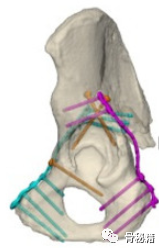

包括前柱螺钉,后柱螺钉,pecten螺钉,magic螺钉等

今天给大家介绍的是髋臼内侧缘螺钉,可谓更加经典。

这些螺钉最重要的特点就是通过前方固定后方,或通过后方固定前方,可谓一夫当关万夫莫开,有立柱顶千斤之用。